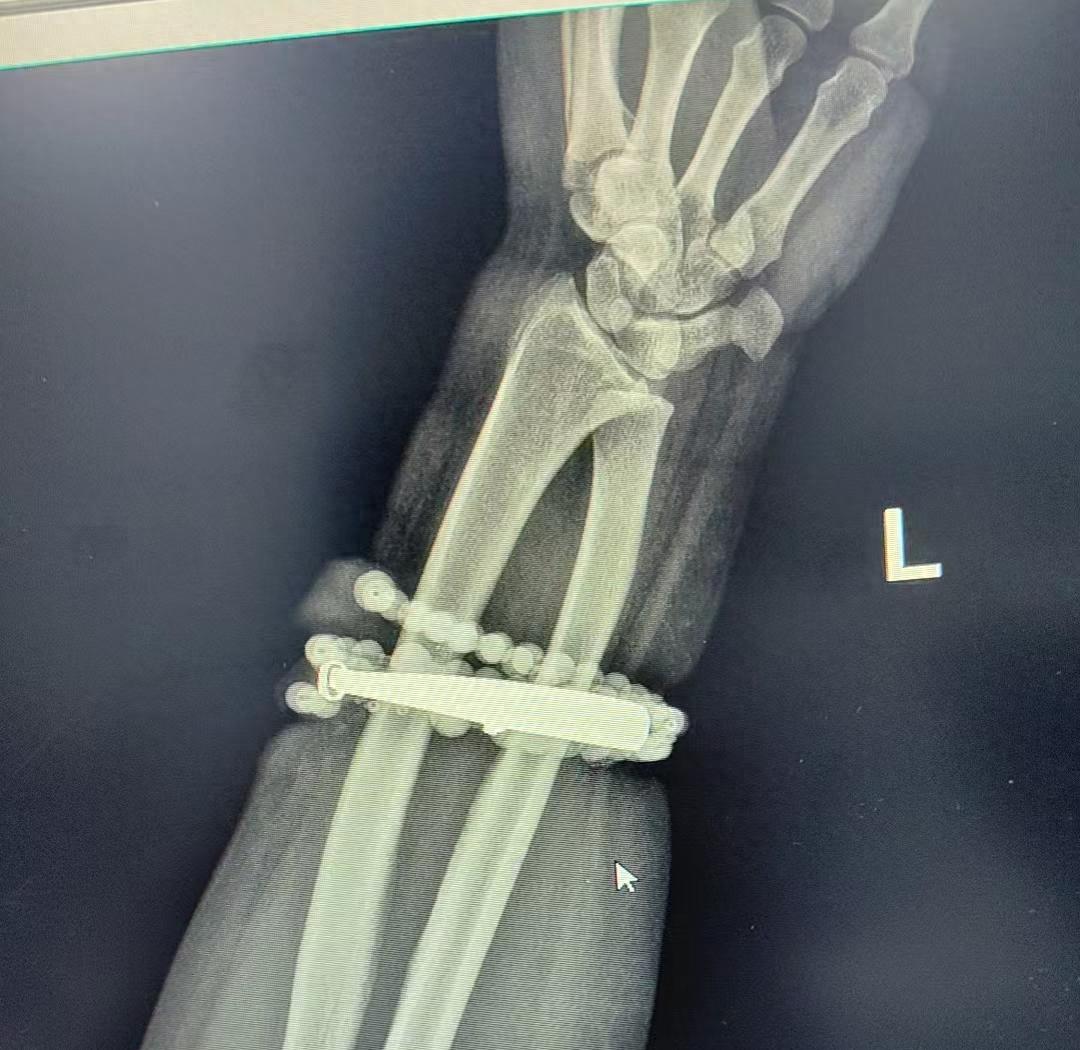

近日在福建宁德,33岁的患者龚女士因长期佩戴首饰不当,导致首饰完全嵌入皮肤并引发严重软组织感染而就医。 龚女士自述,其手腕上的银手镯与串珠近十年几乎从未摘下,随着体重增加,她逐渐感到手腕皮肤勒紧,但未引起重视。  直至近期手腕部疼痛加剧,红肿明显并伴有脓液渗出,她才惊觉手镯与串珠已部分“长”入肉中,无法自行取下。最终,医生通过一个多小时的精细手术,将手镯与串珠从龚女士手腕中剥离而出,并清创引流控制感染,使患者转危为安。  医生提醒佩戴首饰要注意以下几点: 定期检查与清洁:戴首饰(尤其是戒指、手镯)应定期摘下,清洁首饰及佩戴部位的皮肤,保持干燥。 注意“贴合度”:随着体重增加、妊娠水肿等生理状况的改变,应及时调整或取下过紧的首饰,避免压迫局部血液循环。 警惕皮肤信号:佩戴部位一旦出现瘙痒、红肿、疼痛、破溃等不适症状,应立即摘下首饰,观察皮肤情况。若症状持续不缓解,切勿自行用药或“硬扛”,应立即到正规医院就诊。 碰到特殊情况应及时取下:在进行体力劳动、运动或接触化学品,最好取下首饰,避免摩擦、损伤或化学腐蚀。 来源:大象新闻综合福建卫生报、新闻广角、广州日报